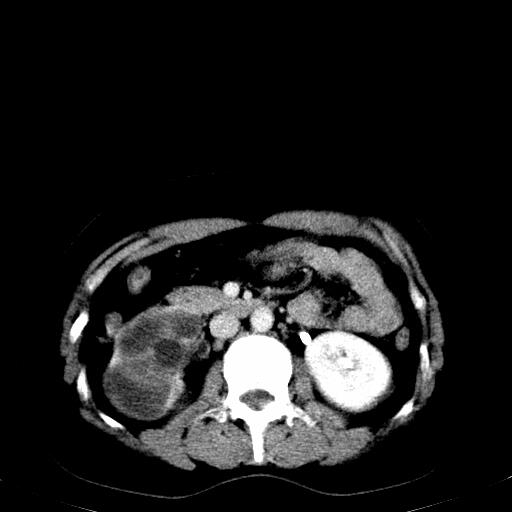

患者体检发现右肾体积增大,怀疑右肾积水

右肾重度积水,以肾盏积水明显,有分隔,上段输尿管轻度扩张,管壁增厚,考虑肾结核可能,请结合尿检查,胸部拍片排除肺结核。

右侧肾积水、左侧肾结石  ,要排除右肾结核可能。

右肾重度积水,建议ct向下扫描或逆行造影,左肾及左输尿管结石 .

要排除右肾结核可能

左肾不是结石,是造影后改变.右肾积水,功能仅存.

右肾积水、左侧肾脏结石,建议进一步检查原因除外左肾结核可能